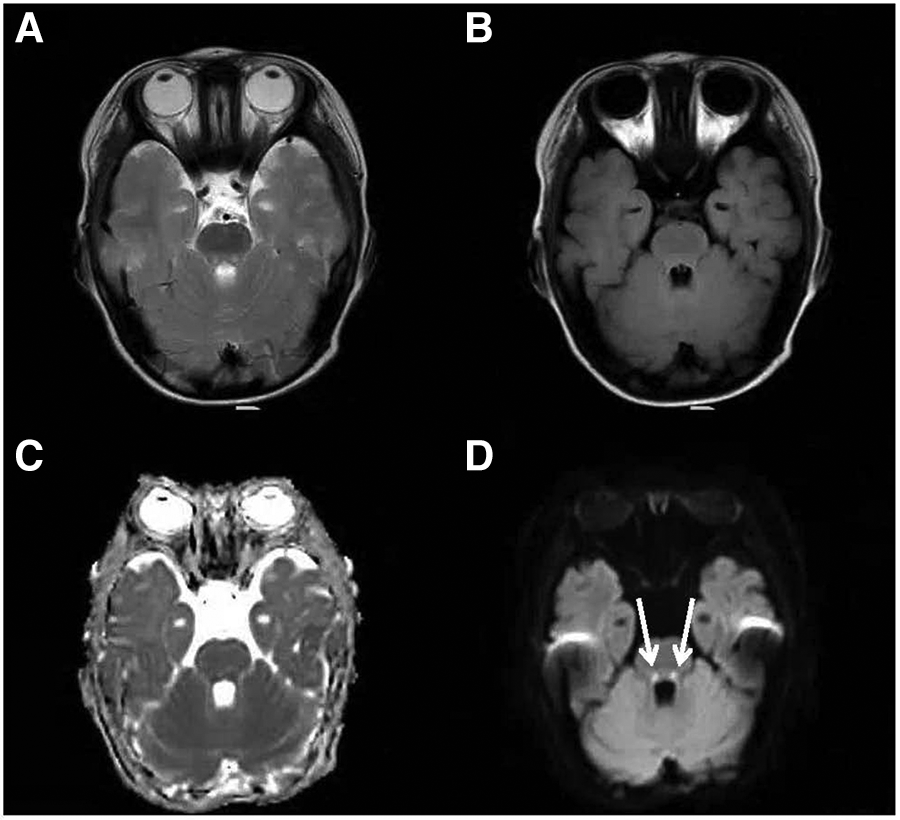

Figure 2

Cranial MRI at the level of the dorsal pons. An axial T2-weighted (A), an axial FLAIR (B), a dADC (C) and a DWI (D) scans are shown and abnormally high signals in DWI in the dorsal pons can be seen (white arrow).